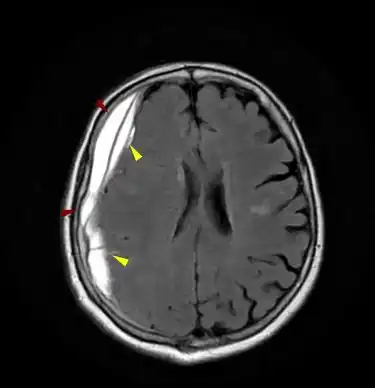

ΕΠΙΣΚΛΗΡΙΔΙΟ (ΚΟΚΚΙΝΑ ΒΕΛΗ) + ΥΠΟΣΚΛΗΡΙΔΙΟ (ΚΙΤΡΙΝΑ ΒΕΛΗ) ΑΙΜΑΤΩΜΑ

Το επισκληρίδιο αιμάτωμα είναι αιμορραγία στην περιοχή μεταξύ του κρανίου και της εξωτερικής από τις τρεις προστατευτικές μεμβράνες που περιβάλλουν τον εγκέφαλο (σκληρά μήνιγγα).

Τα επισκληρίδια αιματώματα, συνήθως προκαλούνται από τραυματική ρήξη αρτηριών.